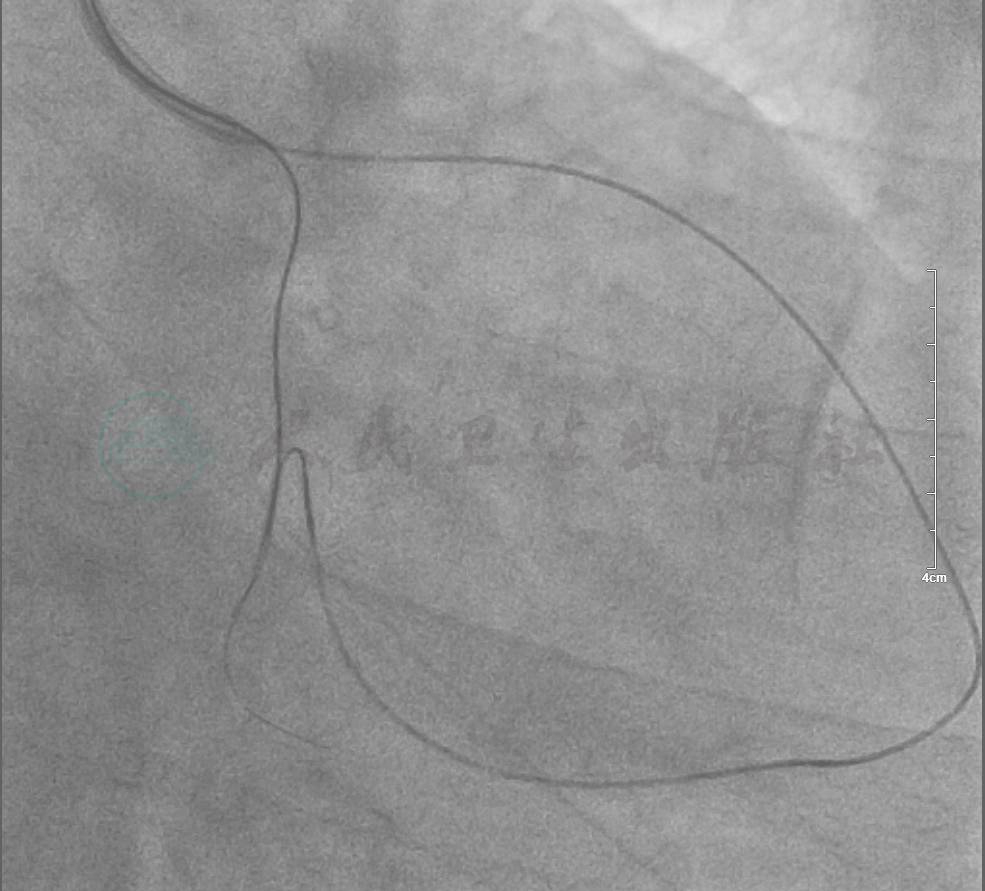

选用右侧桡动脉径路,6F血管鞘。造影发现:右冠中段支架内无再狭窄,左主干内膜光滑无狭窄,左前降支中段完全闭塞,左回旋支近端完全闭塞(图1、图2)。

图2 冠脉造影示左回旋支近端完全闭塞

(RAO 30°+ CAU 30°view)